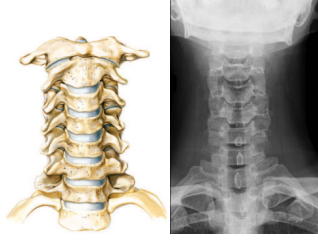

1. AP:

• Raio entra da frente para trás inclinado 20o em

relação ao corpo mas reto em relação à coluna

• Em AP não conseguimos ver C1 e C2 pois ficam

cobertas pela mandíbula

Aparecem as vértebras até C7 (coluna cervical)